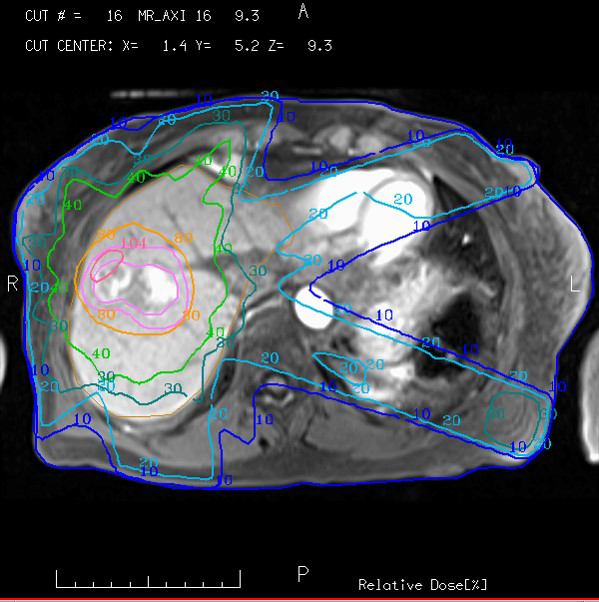

In recent years, we’ve made great strides in optimizing the integration of MRI in Radiation Oncology. In fact, it’s not difficult to imagine a day when MRI becomes the primary method of therapy planning simulation and image guidance for a variety of treatment indications. While CT has long been the preferred modality for radiation therapy due to its geometric reliability and easy conversion to representation of electron density in support of dose calculations, MRI has been a useful adjunct because of its improved ability to discern soft tissue anatomy.MRI is now recommended for volumetric treatment planning in cervical cancer brachytherapy,1 and CT/MRI fusion is now standard practice in radiation therapy. The application of MRI in radiation oncology is not without its challenges, however. In this inaugural issue of the AAPM Research Spotlight, James Balter offers his perspectives on the growing use of MRI for therapy planning, guidance, and assessment treatment response as well as major areas of research and new opportunities provided by AAPM for its members to improve understanding and utilization of MRI in radiation oncology.

Balter explains that larger magnet bores and improved field homogeneity have supported the potential role of MRI in treatment simulation. Numerous studies indicate that quantitative measurements of perfusion, diffusion, and spectroscopy from MR systems may serve as a biomarker for supporting personalized therapy, supporting assessment of treatment and, if necessary, adaptation mid-therapy course. Various efforts are underway to support MRI in place of CT capabilities by providing a synthetic model of the patient that sufficiently represents radiation attenuation and geometric configuration.2 Vendors are making MRI-compatible immobilization as well as laser-based positioning systems. They are optimizing imaging sequences for the needs of radiation oncology and improving the integration of imaging coils with immobilization systems. Most adaptations to MRI scanners to accommodate radiation therapy simulation primarily require software and inexpensive hardware modifications. As most radiation oncology clinics have access to MRI outside of the department, enhancement of such systems is a cost-effective means of supporting MRI-based simulation for smaller departments.